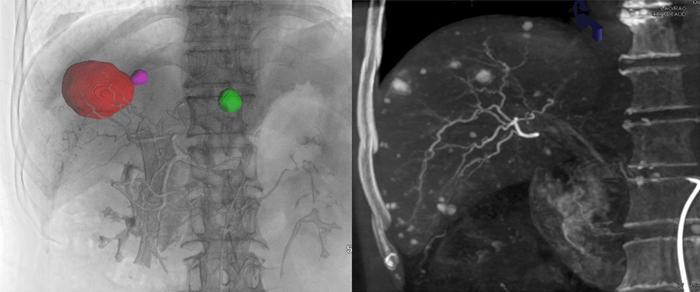

Cone-beam computed tomography stands out as a promising alternative due to its unique volumetric imaging capabilities. CBCT employs a cone-shaped X-ray beam to produce three-dimensional reconstructions of anatomical structures with a level of detail that traditional modalities may not achieve. This enhanced visualization facilitates automatic detection and navigation of targeted vessels, offers real-time fluoroscopic guidance, and enables precise post-TACE assessment of embolization. Recognizing the advantages of CBCT, interventional radiologists are drawn to it as a potential solution to the limitations faced with traditional imaging methods. Despite its advantages, full clinical integration of CBCT continues to be stymied by obstacles such as insufficient awareness among practitioners and a lack of consistency in operational parameters and application protocols.

Image Credits: Cai-Fang Ni, Zhi-Ping Yan, Bin-Yan Zhong, Zhong-Zhi Jia